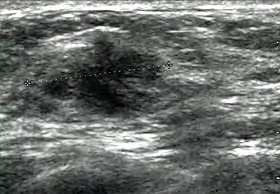

Breast ultrasound is the use of medical ultrasonography to perform imaging of the breast.

It can be considered either a diagnostic or a screening procedure.[1]

It may be used either with or without a mammogram.[2]

It may be useful in younger women, where the denser fibrous tissue of the breast may make mammograms more difficult to interpret.[3]

Breast ultrasound is also used to perform fine-needle aspiration biopsy and ultrasound-guided fine-needle aspiration of breast abscesses.[6] Some women prefer breast ultrasound over mammography because they dislike the pain felt during squeezing or fixing of breast done during mammography for X-ray views. Breast ultrasound is painless procedure. Breast ultrasound is usually done with frequency 7 Megahertz to 14 Megahertz. Breast ultrasound includes ultrasound of axillary tail of breast and sometime it includes ultrasound of axillae also to detect abnormal nodes in axilla because lymphatic drainage of parts of breast occur through axillary lymph nodes.